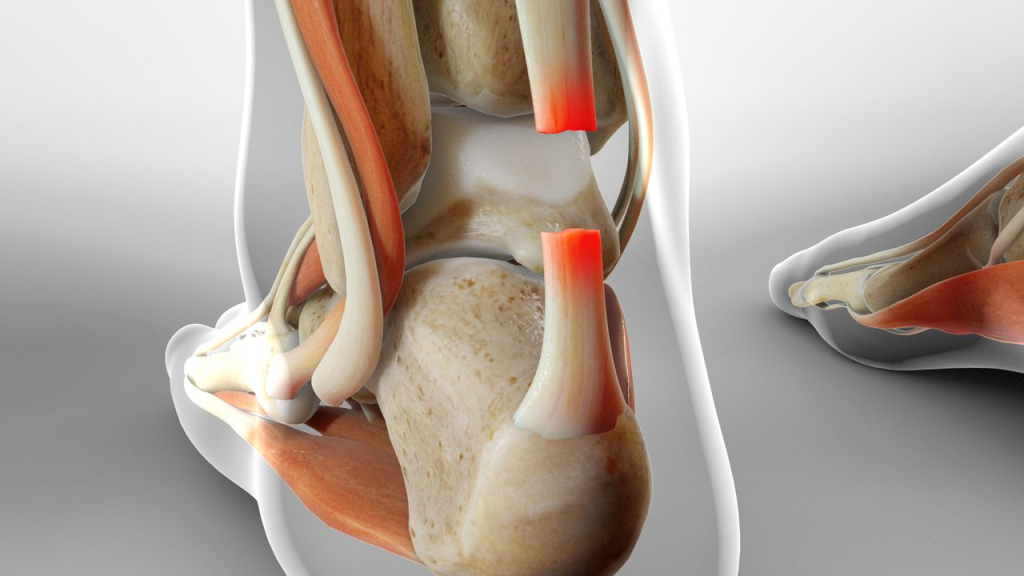

تاندون آشیل چیست و چرا اینقدر مهم است؟

تاندون آشیل قویترین تاندون بدن است که عضلات ساق را به استخوان پاشنه وصل میکند و برای راه رفتن، دویدن و پریدن نقش حیاتی دارد

طبق تجربه بالینی، بسیاری از بیماران متوجه نیستند که تقریباً هر حرکت فعال مچ پا به آشیل وابسته است. به همین دلیل آسیب به آن، زندگی روزمره را بهطور جدی مختل میکند.

پارگی تاندون آشیل پا چیست؟

پارگی تاندون آشیل پا یعنی آسیب ناقص یا کامل تاندونی که عضلات ساق را به پاشنه متصل میکند. این آسیب معمولاً با درد ناگهانی، ضعف مچ پا و ناتوانی در ایستادن روی پنجه همراه است.